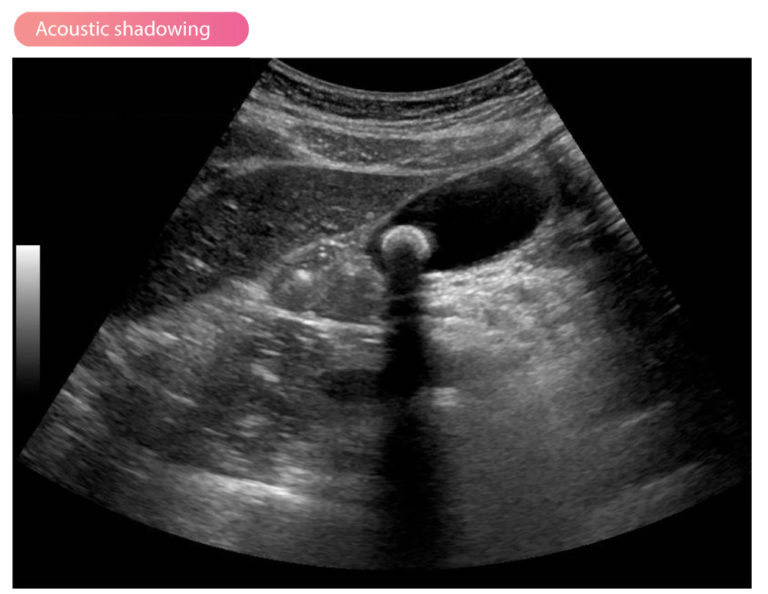

What Does A Shadow Mean On An Ultrasound . a shadow just means that the sound waves were reflected. it will also cast a shadow onto the objects behind (distal to) it. Remember what the shades of black, white and gray mean. A shadow simply means that the sound waves were reflected. Many things can cause shadowing, such as calcifications, air and. acoustic shadowing (sometimes referred to as posterior acoustic shadowing) is a form of ultrasound artifact. what does shadow on ultrasound mean? the area of pleural effusion is framed within four regular borders: It is characterized by the. Much like behind the bucket in our attic, there are dark areas on the ultrasound. acoustic shadowing occurs when an ultrasound beam encounters a highly reflective or dense structure within. The possible significance of light/dark spots in. does a shadow or black spot on my kidney scan mean cancer? It can be caused by many things,. As covered earlier, it’s important to remember that different colors.

acoustic shadowing occurs when an ultrasound beam encounters a highly reflective or dense structure within. Much like behind the bucket in our attic, there are dark areas on the ultrasound. Remember what the shades of black, white and gray mean. A shadow simply means that the sound waves were reflected. the area of pleural effusion is framed within four regular borders: The possible significance of light/dark spots in. It is characterized by the. a shadow just means that the sound waves were reflected. does a shadow or black spot on my kidney scan mean cancer? acoustic shadowing (sometimes referred to as posterior acoustic shadowing) is a form of ultrasound artifact.